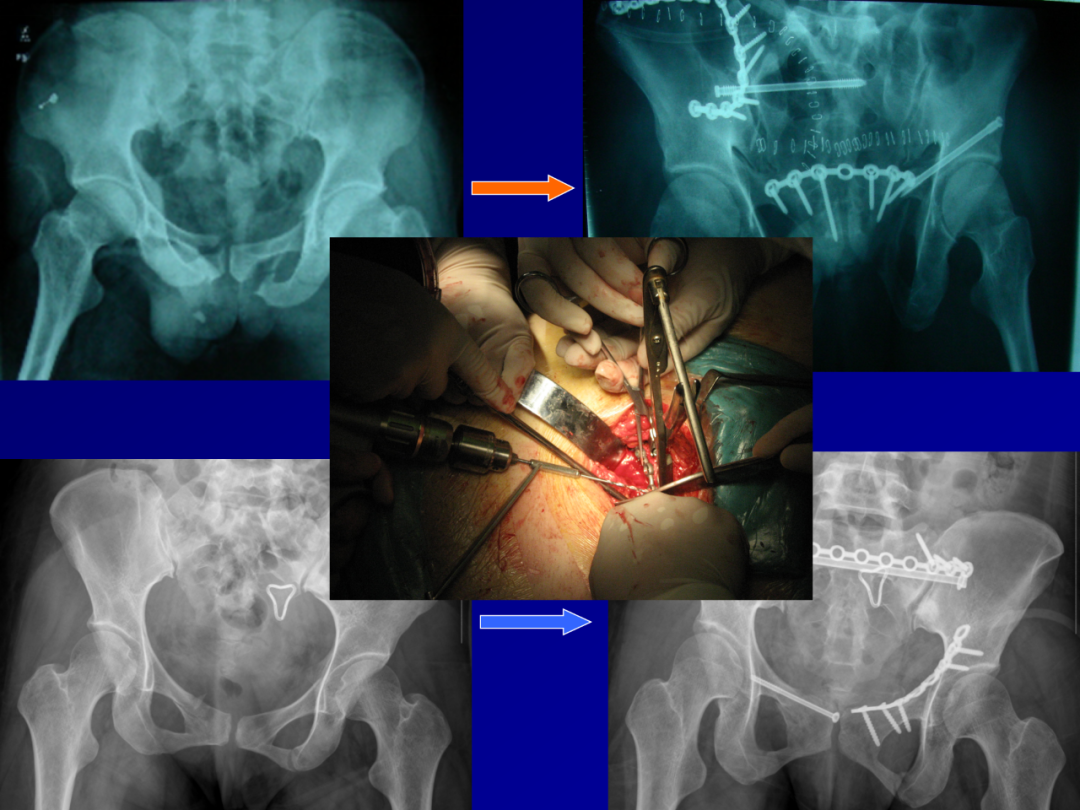

364例复杂骨盆骨折带你掌握内固定技术!